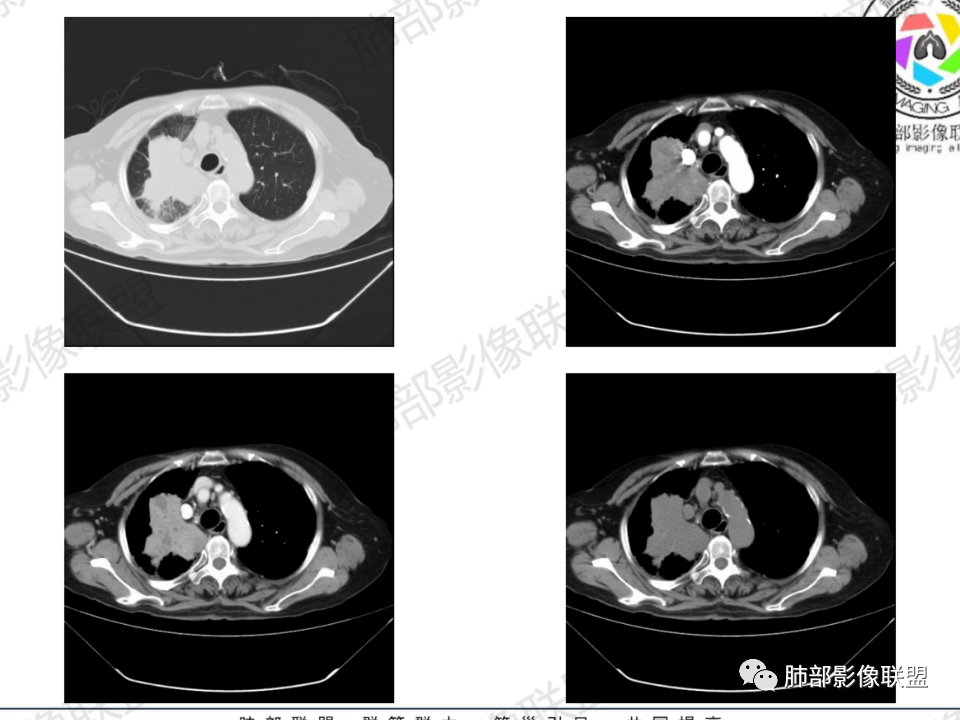

右肺体积小,提示既往结核

支气管影

前,后段都在,没有堵塞

支气管壁增厚,周围磨玻璃边界不清,提示炎症。胸膜下钙化符合结核

近期发热符合感染

这个层面往上应该是尖段,显示不清

背段支气管周围增厚伴钙化,符合结核改变

胸腔积液并胸膜钙化,符合结核;

结核是肯定有。现在最大问题是尖段

近端显示不清,但是远端是粘液栓,可以认为是还行的

如果是近端鳞癌,远端应该会堵塞,不会整个肿块里面还有较为通畅的支气管

这个区域我们看到密度与周围一致,并不是肺癌伴周围不张的感觉,所以鳞癌暂时是不支持的